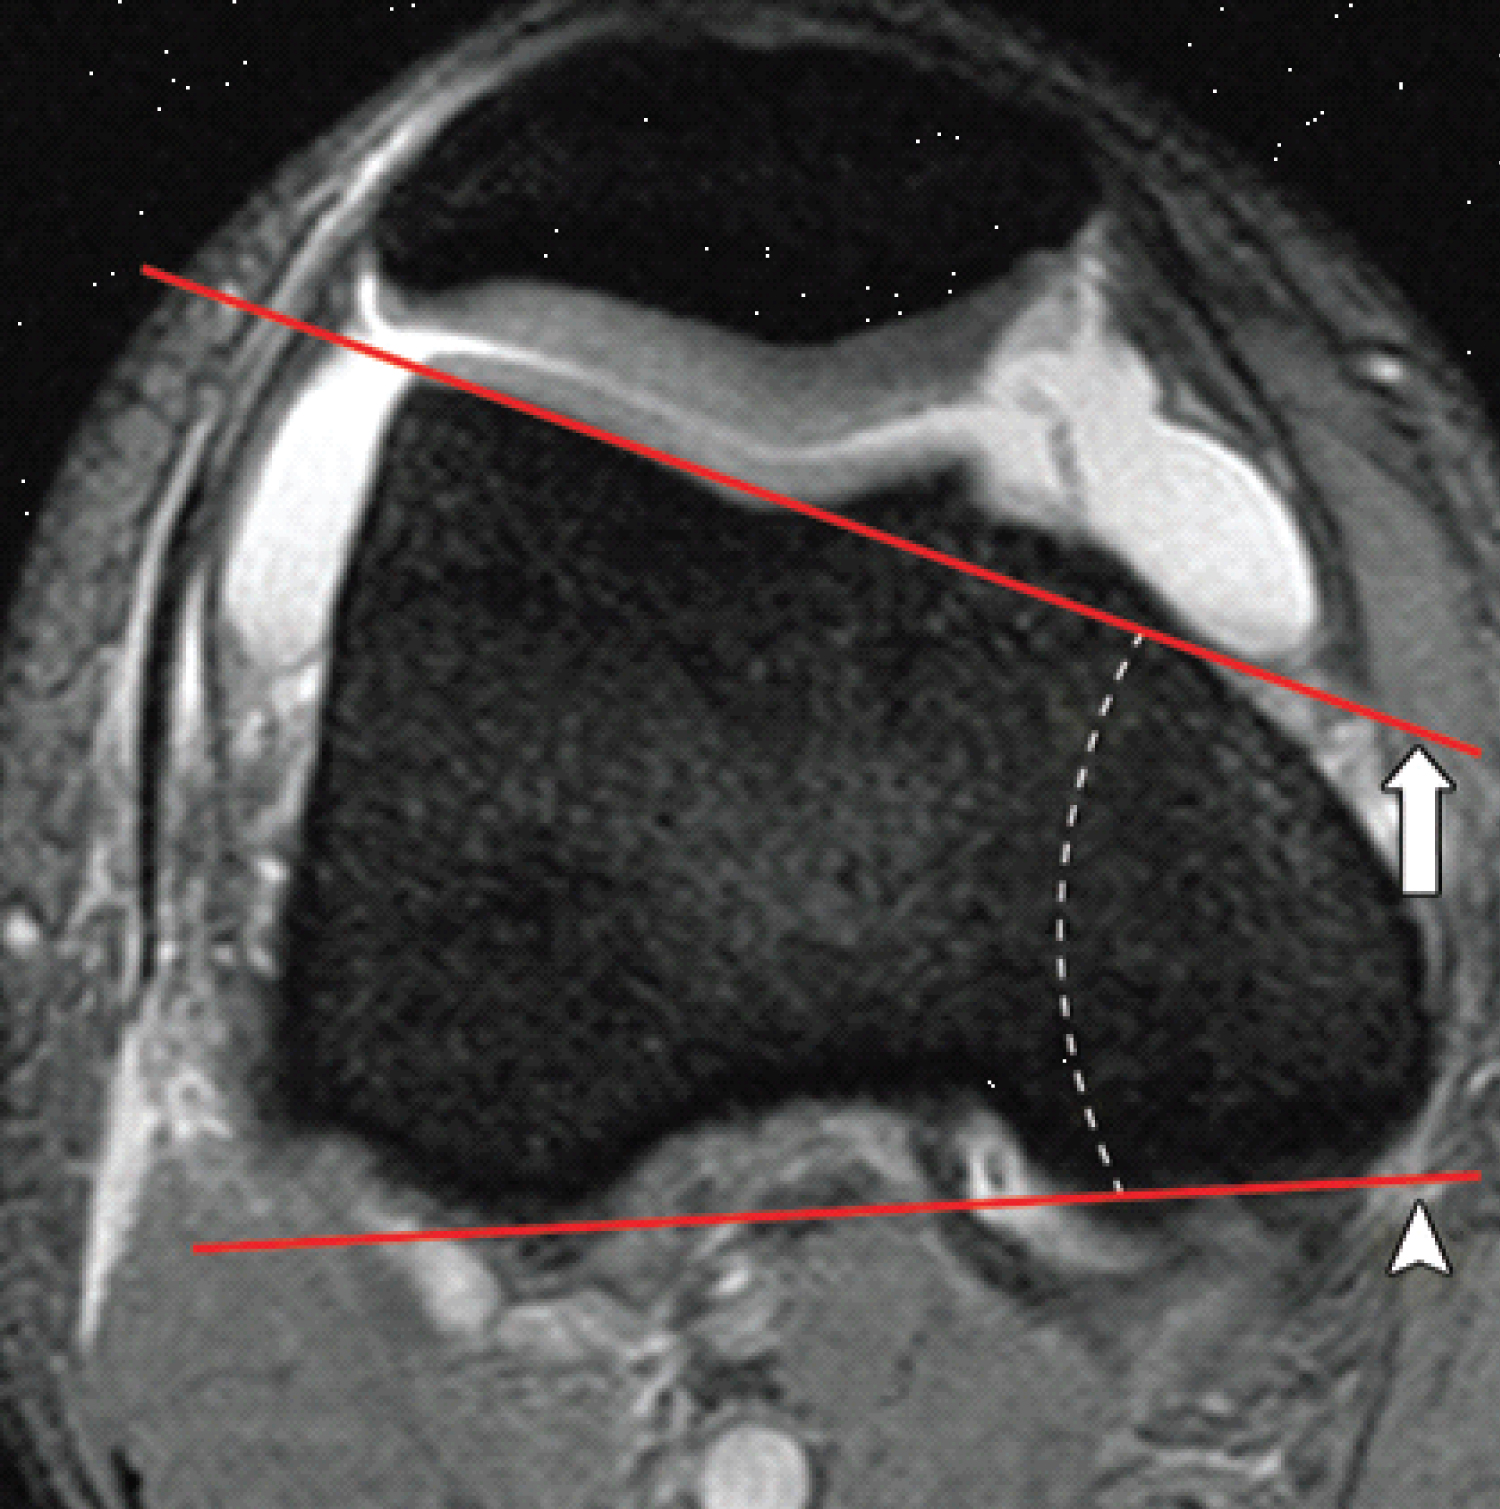

a) Lateral trochlear inclination (LTI), on the MR-slices at about 3 cm above the femorotibial joint space by measuring the angle between a line tangential to the subchondral bone of the posterior aspects of the femoral condyles and a line tangential to the subchondral bone of the lateral trochlear facet (Figure 3). An angle of < 11° is considered abnormal [5].

Figure 3: Lateral trochlear inclination assessed on axial fat-saturated T2-weighted MR images. A line (arrow) is drawn along the subchondral bone of the lateral trochlear facet, and a second line (arrow head) is drawn along the posterior aspect of the femoral condyles. The angle between the two lines is the inclination angle (dashed line). An inclination angle of less than 11° indicates trochlear dysplasia. View Figure 3